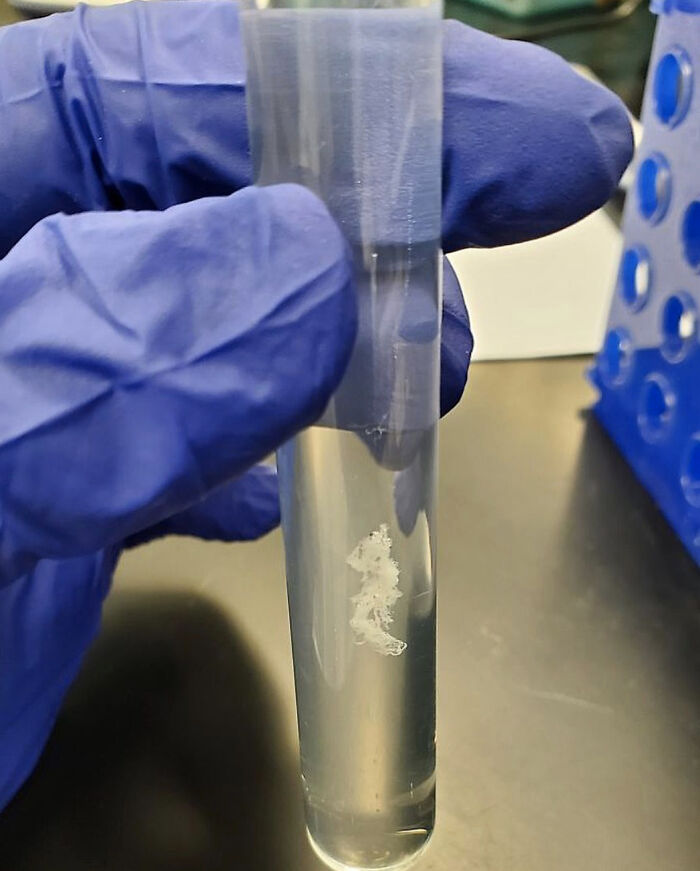

This Is How Purified DNA Strands Look In A Test Tube!